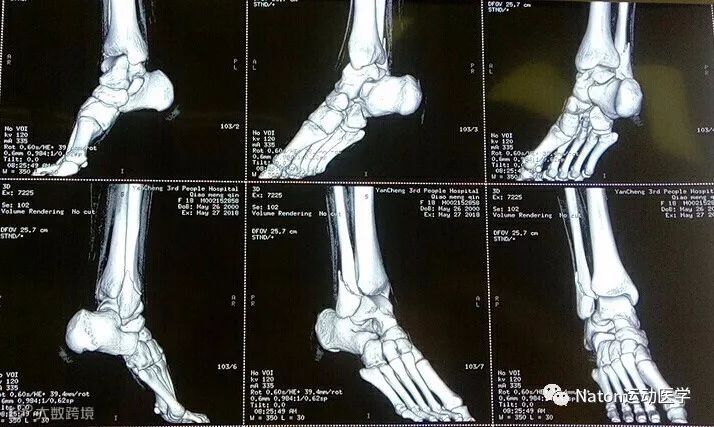

术前影像